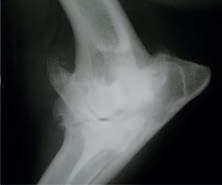

En la exploración general, el paciente se encontraba cubierto de suciedad, barro, heces, orina y saliva. Presentaba taquipnea, sialorrea densa y edema del labio inferior derecho (Figs. 2 y 3). Adicionalmente, el animal mostraba prurito con signos de rascado intenso en tronco, cabeza y hueco axilar y se mantenía inquieto, con vocalizaciones y ataxia. Al contacto con el

A B C d

NEIKER confirmó la afectación por EA mediante PCR en encéfalo positiva y tonsila no concluyente (Anexo 2). La necropsia informó de intenso edema en la cabeza y zona intermandibular. Se observó alopecia por rascado en hocico, zona ventral del cuello y extremidades.

Figura 2. Intensa sialorrea en el caso 2. Figura 3. Edema de la mucosa labial (rascado) en el caso 2.